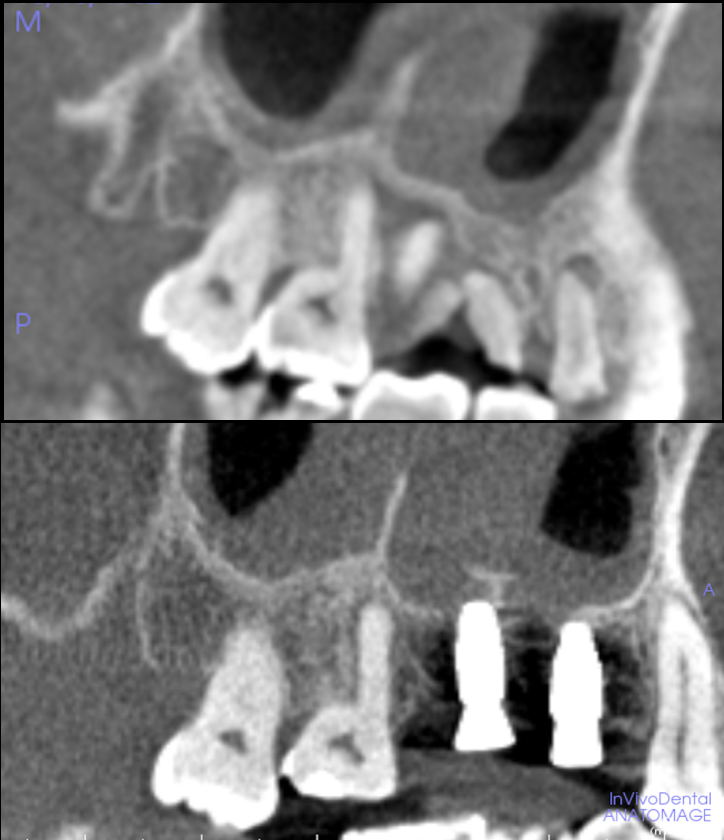

担当医 荻原太郎 すでに入っているインプラント...